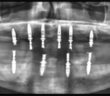

CHIRURGIE IMPLANTAIRE GUIDEE : PRINCIPES FONDAMENTAUX, FLUX DE TRAVAIL NUMERIQUE ET INTEGRATION CLINIQUE

AORALSCAN ELITE : INTÉGRER LA PHOTOGRAMMÉTRIE AU FLUX IMPLANTAIRE DU CABINET